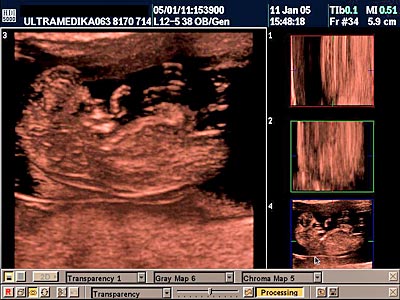

B) Drugi marker je registrovanje postojanje povećane debljine prozračne zone (NT) u vratu ploda-embriona. Obično greške nastaju kada se kontura vrata ploda ne razlikuje od amniona - opne u kojoj se plod nalazi. Osim znanja doktora, rezolucija slike Ultrazvučnog aparata čini ključnu ulogu u merenju ove strukture. Ona-NT se meri u periodu od 9 do 14 GN. Iako je najveća normalna debljina NT 2,5 mm na kraju 14 GN ova vrednost NT može ukazivati na trizomiju ako je registrovana na početku ovog vremenskog perioda. Samo Ultrazvučna kompjuterizovana tomografija može u velikom procentu pouzdano izmeriti ovu strukturu i to na dva načina. Pregled endovaginalnom sondom Braund-band od 8-4MHz, često zbog pozicije ploda nije u stanje da adekvatno registruje NT. Pregled se može znatno zbog toga produžiti i ne mora tačno izmeriti debljinu NT. Međutim u ovakvim situacijama upotrebom Braund-band sondi koje koriste ceo opseg ultrazvučnih talasa od 12 do 5 MHz, pregled se u velikom broju slučajeva završava pregledom preko prednjeg trbušnog zida. Ovaj transabdominalni pregled ima prednosti zbog mogućnosti boljeg pozicioniranja ultrazvučne sonde

u odnosu na položaj ploda, pri čemu je kvalitet slike neuporedivo bolji u odnosu na pregled vaginalnom sondom. Jedino konstitucija trudnice donekle ograničava pregled preko prednjeg trbušnog zida (mokraćna bešika ne mora biti puna).

Povećana debljina NT uz neadekvatnu frekvencu srčanog rada embriona otkriva oko 80 % oštećenih plodova. Važnost ovog ultrazvučnog markera je i u tome što mnoga oštećenja građe ploda takođe bivaju praćena neadekvatnom debljinom vratne regije ploda.